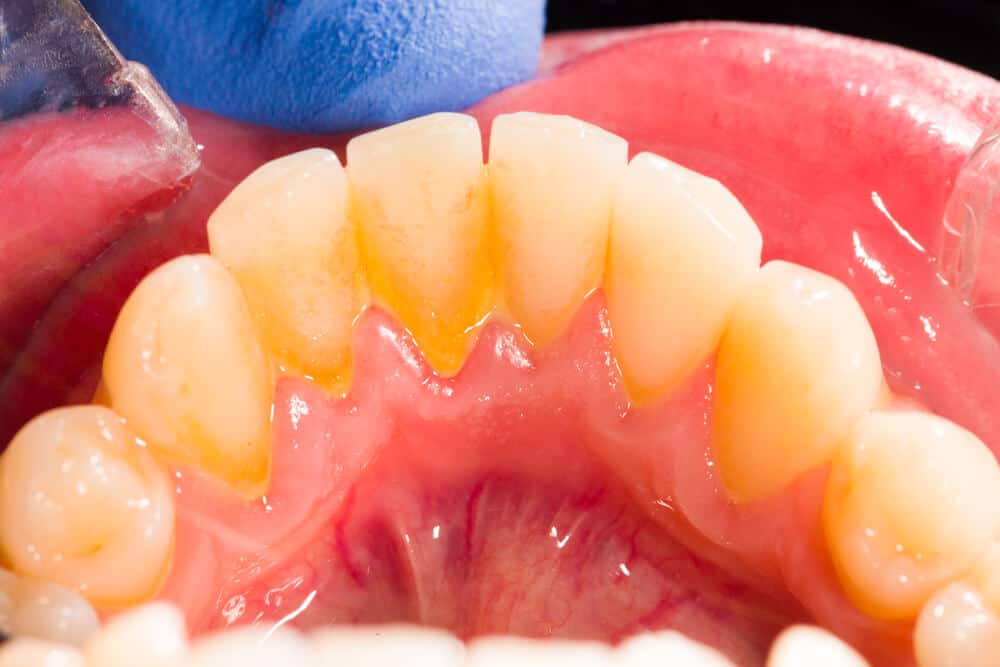

What Is The Build Up On My Teeth . calcium buildup might refer to plaque and tartar that can collect and cause decay if left on teeth. Yellow, brown or black stains on your teeth. If plaque is not removed on a regular basis, it will harden and form visible calcium deposits (tartar). if you start to develop tartar on your teeth, you might notice: dental calculus, also known as tartar, is a hardened form of dental plaque that can build up on your teeth over time. the buildup of plaque and tartar on the teeth can cause bad breath, tooth decay, and gum disease. A white, yellow, or brown buildup. calcium buildup—also called calcium deposits, tartar, or calculus—are hardened patches of plaque that form on the teeth. Learn the ways to prevent plaque and tartar at home. Keep reading to learn about. A chalky, gravelly, or fuzzy feeling when running your tongue over your teeth. It might also refer to problems with calcification of enamel. If you have a buildup of calculus on your teeth or gums, you may notice: Persistent bad breath (halitosis) or foul taste. Plaque is a sticky film that coats teeth and contains bacteria.